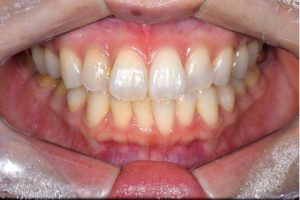

症例写真(治療前)

担当医師所見

治療前:

八重歯が目立ちます。また銀歯もおおく、見た目が気になります。虫歯も散見できます。

症例写真(治療後)

矯正装置をつけています。だんだん八重歯が動いてきているのがわかります。今回のケースでは、抜歯を行わずに矯正ができました。

治療後:

矯正治療と虫歯の治療すべて終わったときの写真になります。見た目も最初の頃とは全く違いますし、お口の中もすごく綺麗です。

治療

方針

まずは虫歯の治療を行い、被せ物をする部分は仮歯をいれて矯正を行う。矯正終了後、仮歯の部分を最終的な被せ物に変えていく。また気になっていた銀歯もセラミックに変えて終了となった。

内容

セラミックインレー、オールセラミックプレミアム、矯正